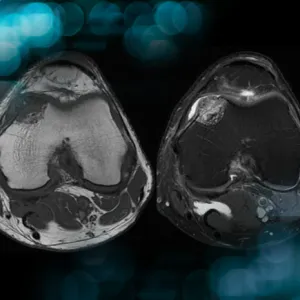

Explore the case of a patient with knee pain, revealing more than just an injury, and uncover the management strategies for osteolytic lesions of the distal femur affecting the knee joint

This video shows how to manage a subchondral cartilaginous tumor in the distal femur surgicaly, from resection tips to grafting cut and fixation technique.